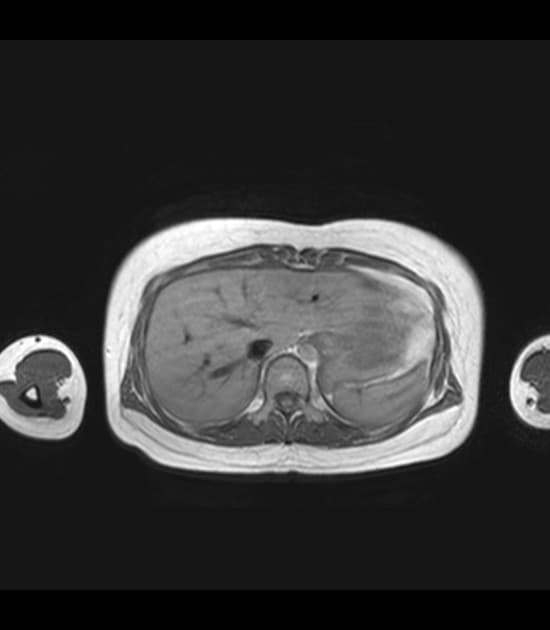

- Bệnh cơ tim phì đại dạng đỉnh thất (apical hypertrophic cardiomyopathy) với tắc nghẽn ở đoạn giữa thất (midventricular obstruction).

- "Bệnh cơ tim phì đại dạng đỉnh thất là thể hiếm, đặc trưng bởi phì đại cô lập ở đỉnh thất trái."

Bệnh cơ tim phì đại dạng đỉnh thất là một thể hình thái riêng biệt của bệnh cơ tim phì đại do bất thường sợi co cơ, chủ yếu ảnh hưởng đến đỉnh thất trái. Khác với thể phì đại vách không đối xứng phổ biến hơn, thể này biểu hiện bằng sự dày lên cô lập ở vùng đỉnh, thường dẫn đến tắc nghẽn đoạn giữa thất và tạo gradient áp lực. Tình trạng căng thẳng huyết động này có thể gây thiếu máu cơ tim vùng đỉnh, hoại tử lớp dưới nội tâm mạc và xơ hóa thành thất dạng ổ, như thấy trên hình ảnh cộng hưởng từ tăng sáng muộn. Sự hiện diện của mô xơ liên quan đến nguy cơ cao hơn về rối loạn nhịp và các biến cố tim bất lợi, làm tiên lượng có thể xấu hơn. Chẩn đoán phân biệt bao gồm nhồi máu cơ tim, bệnh cơ tim do amyloid và sarcoid, nhưng hình ảnh đặc trưng dạng 'bích' trên chụp buồng thất trái và sự vắng mặt của bệnh động mạch vành giúp khẳng định chẩn đoán.